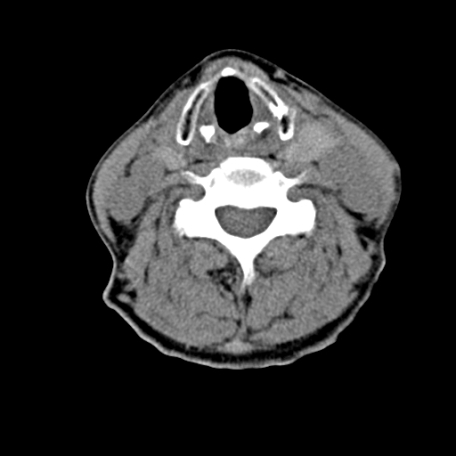

标题: CT24010:患者女56岁双侧甲状腺摘除术后一月复查,患者现感 [打印本页]

标题: CT24010:患者女56岁双侧甲状腺摘除术后一月复查,患者现感

甲状腺术后复发,现在甲状腺区域仍有密度不均匀之软组织密度影。

甲状腺区域密度不均匀密度影,应该是术后改变,要鉴别是否复发,建议增强检查。

“甲状腺摘除术后一月复查”,有病理吗?考虑术后复发,可能是恶性,颌下及左侧颈部淋巴结有肿大。

考虑术后复发,并颈部淋巴结肿大。请结合临床。

双侧甲状腺肿大,周围结构不清,术后复发时间有点短,考虑出血并感染。